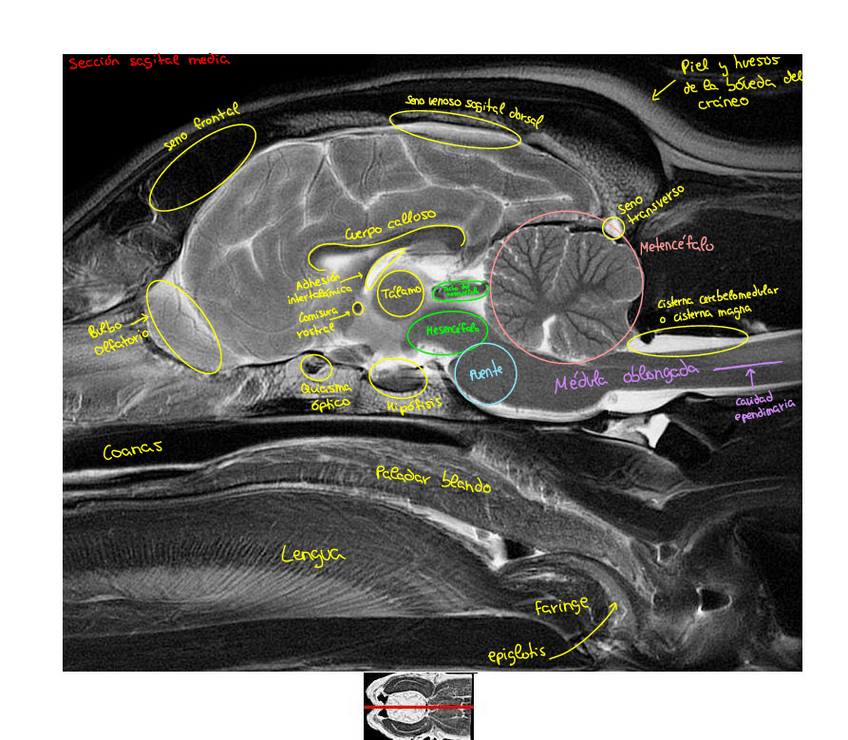

Imagenes-secciones-Resonancia-magnetica-cabeza-perro.pdf

Apuntes - Imagenes-secciones-Resonancia-magnetica-cabeza-perro.pdf